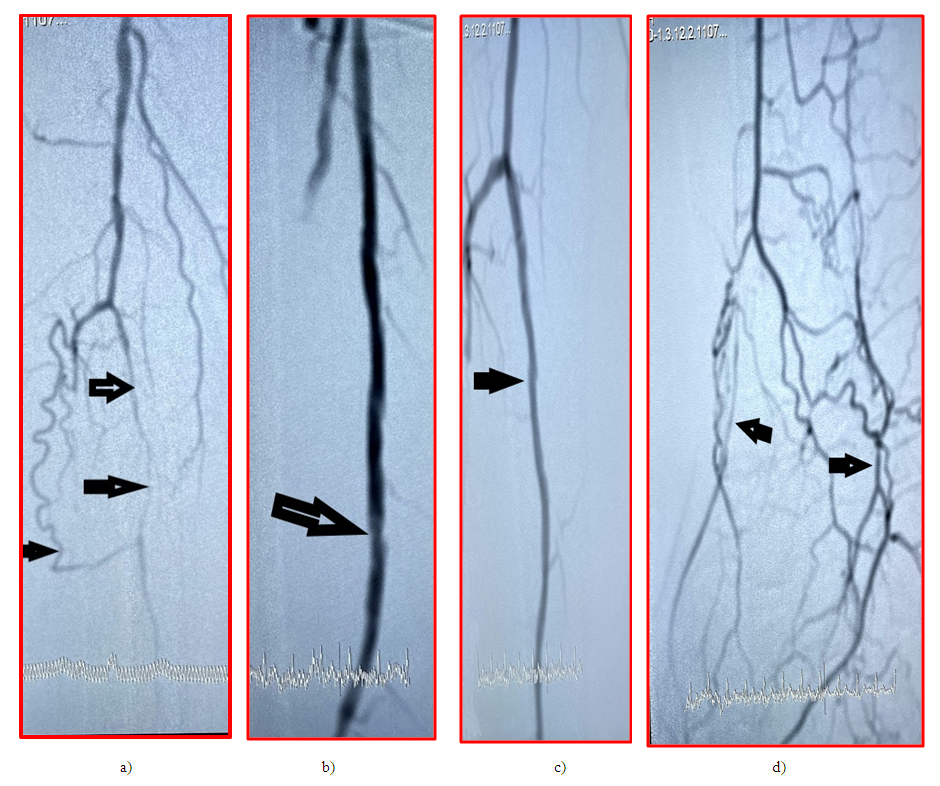

| Figure 4. Digital angiography a) all the tibial arteries are occluded, the distal part of the PA is contrasted through the collaterals (arrow), b) control arteriography after recanalization and balloon angioplasty of the SFA (arrow). c) through the collateral arteries of those feeding from the PA (arrow) on the foot, the plantar arteries (purple arrow) and the dorsal artery of the foot (green arrow) are contrasted |